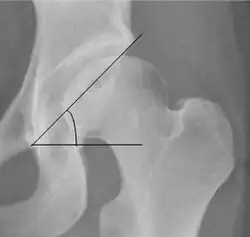

| Center-edge angle of Wiberg | ![]() |

The superior-lateral coverage of the femoral head. | |